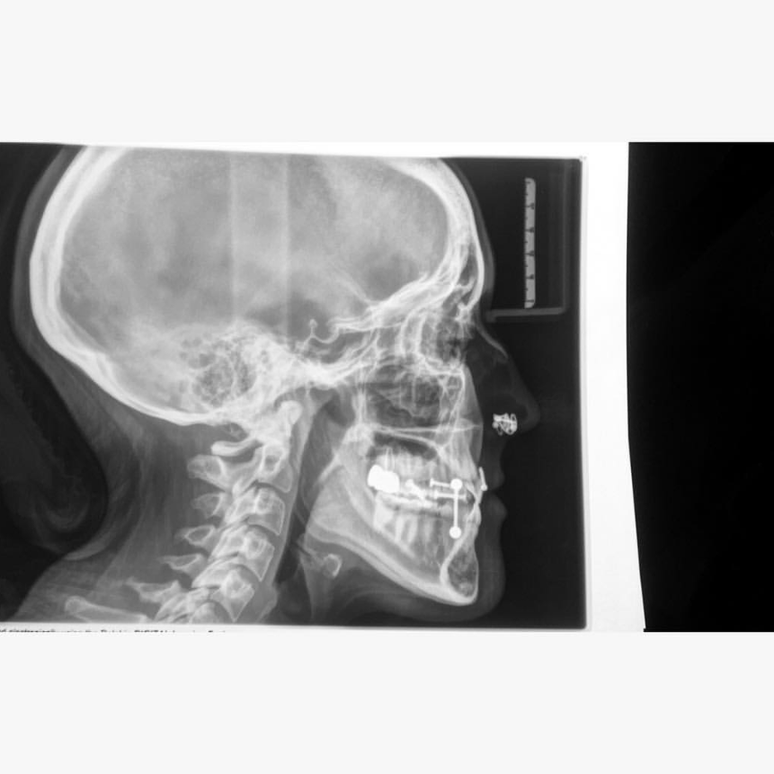

Jewelry And X Rays . Web remove any jewelry or metallic items you have on. Web it is common to see jewelry artifacts on imaging examinations, most commonly plain radiographs, although also on other modalities, where they. Web by avoiding production of these artefacts when possible, we can reduce radiation.

Web it is common to see jewelry artifacts on imaging examinations, most commonly plain radiographs, although also on other modalities, where they. Web by avoiding production of these artefacts when possible, we can reduce radiation. Web remove any jewelry or metallic items you have on.